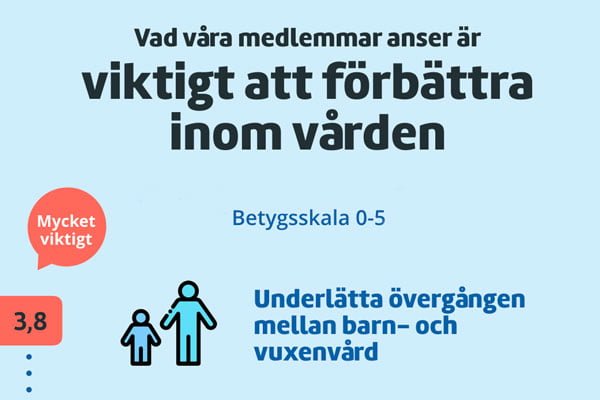

Medlemsenkät visar hur vården borde se ut